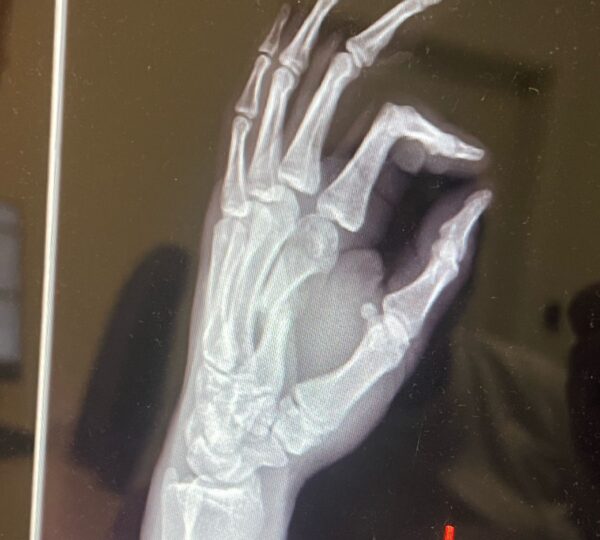

• Zranenie: 4. 6. 2024 – zlomená zaprstná kosť

• Operácia (osteotómia): 27. 10. 2024

Osteotómia je chirurgický zákrok, pri ktorom sa kosť prerezáva a presne nastaví tak, aby mohla správne zrast. Po takejto operácii predstavuje hlavnú výzvu najmä kvalita zhojeného kostného tkaniva, opuch, bolesť a obmedzenie pohyblivosti. Práve terapia LIMFA tu zohrala kľúčovú úlohu.

1. Rýchlejší ústup opuchu – podporený stimuláciou poškodených buniek.

2. Zlepšenie kvality tkanív – regenerácia mäkkých tkanív aj kostí.

3. Obnova mobility ruky – rýchlejší návrat flexibility a sily.